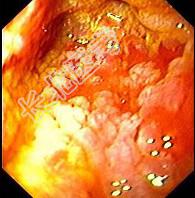

- 单项选择题男性,67岁, 反复上腹饱胀不适2年,以餐后为甚, 伴反酸、嗳气、食欲不振、恶心、呕吐等。胃镜检查胃窦粘膜见散在灰白色斑块,如图: 该病人最可能的诊断是 ( )

A、胃黄斑瘤

B、慢性浅表性胃炎

C、慢性萎缩性胃炎伴肠上皮化生

D、胃泌素瘤

E、消化性溃疡